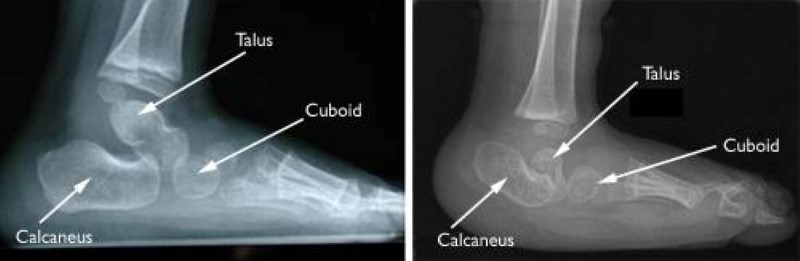

x-rays of normal foot and vertical talus

(Left) An X-ray of an infant's foot showing normal bone position. In this X-ray, the talus is pointing toward the toes. (Right) An X-ray of an infant's foot with vertical talus. In this X-ray, the talus is pointing straight down.

(Left) Courtesy of Texas Scottish Rite Hospital for Children (Right) Courtesy of Campbell Clinic Orthopedics